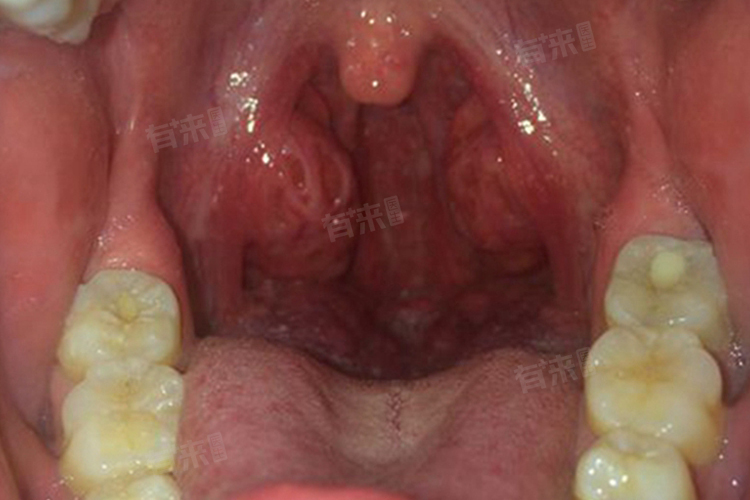

- 不同类型的扁桃体发炎,引发咳嗽的情况有所不同。急性扁桃体发炎起病急,炎症反应剧烈,扁桃体红肿明显,表面常有黄白色脓性分泌物。此时,由于炎症刺激强烈,咳嗽症状往往较为明显,可能伴有咽痛、发热等症状。而慢性扁桃体发炎,炎症相对较隐匿,扁桃体长期处于慢性充血状态,虽然咳嗽症状相对较轻,但可能会持续存在,在患者过度用嗓、进食刺激性食物后,咳嗽可能会加重。

扁桃体发炎导致的咳嗽具有一定特点,咳嗽多为刺激性干咳,初期可能无痰,随着病情发展,若炎症蔓延至气管、支气管,可能会出现少量白色黏痰。咳嗽在晨起和夜间平卧时可能会加重,这是因为晨起时,经过一夜的睡眠,咽喉部积聚的分泌物增多,刺激加重;夜间平卧时,分泌物更容易反流至气管,从而引发咳嗽。